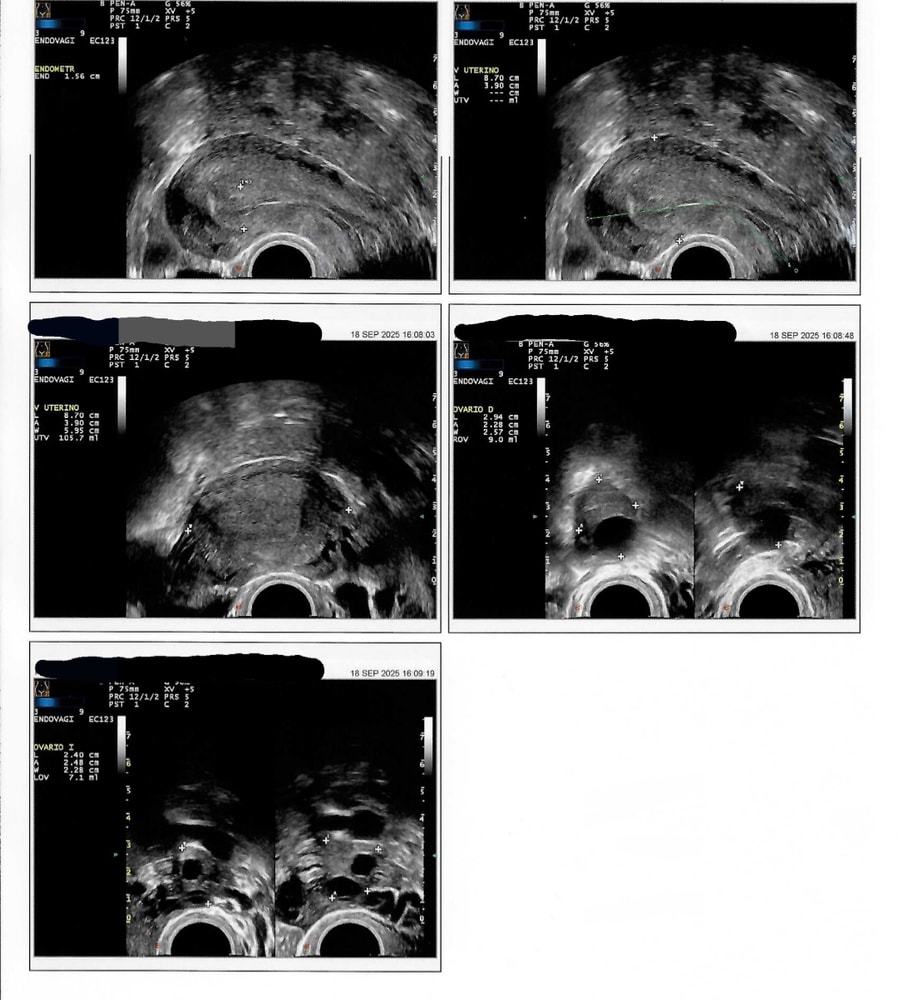

Девочки, меня совсем запутали. И мой врач, и мой организм. Сегодня 42 ДЦ. Месячные обычно приходят на 24-30 день. Но в этом цикле я решила задозировать себя био прогестероном (крем). Думала, что после овуляции хорошо будет для имплантации (если случится). Но, видимо, я заблокировала таким образом овуляцию. Была на УЗИ в четверг. Врач ничего не сказал про фолликулы. Прогестерон пришёл 0.58. И еще сегодня у меня вдруг "пикает" тест на овуляцию 😱 а я жду месячные. Кто видит фолликулы? Нужно ли на мужа прыгать? Или ждать месячные все таки? ))

Ольга, да я вот уже поняла, что просто так его нельзя как везде пишут :( что скажете по поводу узи? Вам видны фолликулы? Я вот не знаю, что делать. Жду месячные, а лг пикает. Фигня какая-то

Oliffka, а что вам сказал врач УЗИст? На фото не понятно то-ли там доминантный фоликул, то-ли жёлтое тело. Но если вам тест на овуляцию предаёт знак, значит был выброс ЛГ, а это значит что в течении 36 часов произойдёт овуляция. Я б на вашем месте времени не теряла😉 возможно прогистерон затормозил рост фоликула. Не принимайте больше прогистерон, через 2-3 дня сходите ещё раз на УЗИ. Если врач обнаружил жёлтое тело, овуляция была. Вот тогда возобновите прём.

Ирэн, в описании узи ни слова про фолликулы. Только размеры яичников. Эндометрий 1.56см, что довольно толсто для начала цикла. Думаю, что на этом фоне врач сделал вывод, что это конец цикла, поэтому про фолликулы ни слова. Но я их вижу на узи